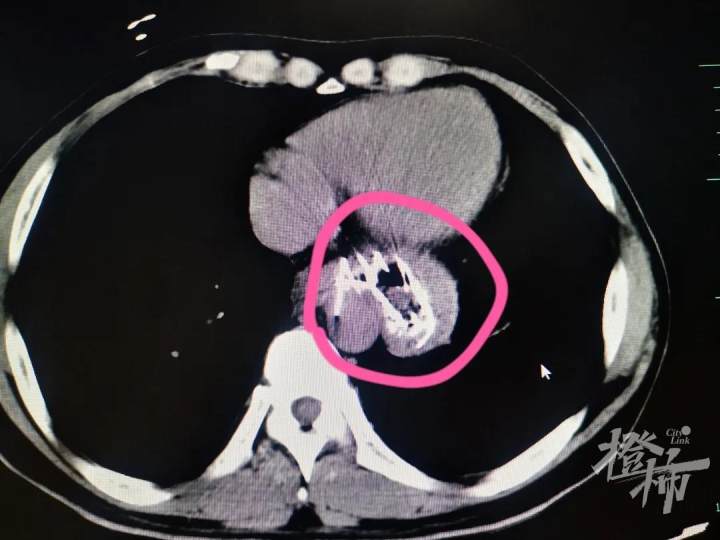

峰哥吓坏了,连忙赶到当地医院就诊,经过CT检查,医生发现峰哥食管、胃部甚至十二指肠处都有不少长条状的尖锐金属异物。

根据CT显示,峰哥体内的“钢针”取出难度太大,当地医院建议他立即转到上级大医院进行治疗。于是,家人又马不停蹄地把峰哥送到了浙江大学医学院附属第一医院。

“患者来的时候情况不太好,虽然生命体征还算平稳,但是根据我们对他进行的增强CT显示,患者贲门处、胃里、十二指肠等多处都有散架的金属支架扎入其中,有一根甚至已经贴着胸主动脉,一旦戳破主动脉,就会造成大出血,万分凶险,危及生命。”峰哥的主管医生——消化内科章粉明主治医师说起他的病情至今仍心有余悸。峰哥被紧急收治住院。